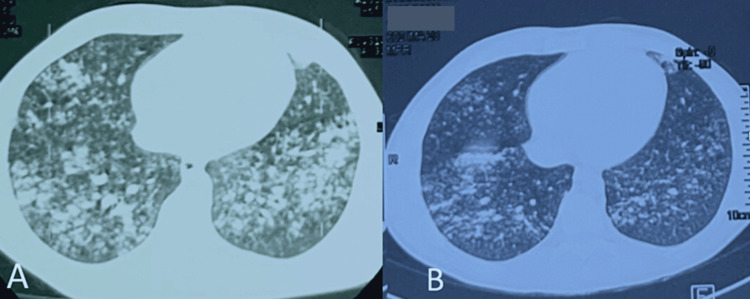

Based on the clinical presentation, radiological findings, and exclusion of infectious etiologies, a diagnosis of e-cigarette and vaping-induced lung injury (EVALI) was suspected. The patient’s history of heavy e-cigarette and vaping product use further supported this diagnosis. The patient was immediately started on supplemental oxygen, and broad-spectrum antibiotics to cover potential bacterial infections. Supportive measures, including intravenous fluids and administation of glucorticosteroids, cessation of vaping was initiated. The patient was put on long-term oxygen therapy 4 L/ min, corticotherapy 20 mg: three times a day, and antibiotic therapy (amoxicillin + clavulanic acid: 3 g/day. After 14 days of treatment, clinical, biological improvement and radiographic changes were noted (Figure 3). There was an improvement in respiratory rate and saturation from 88% to 93% in room air, white blood cells from 25020/mm3 to 16000/mm3 and CRP from 305.58 to 18 and radiological cleaning with persistence of bronchogenic micronodules with subpleural border. HRCT confirms multiple bilateral pulmonary micronodules (A) with radiological improvements after one week of oral corticosteroid treatment (B) (Figure 3).